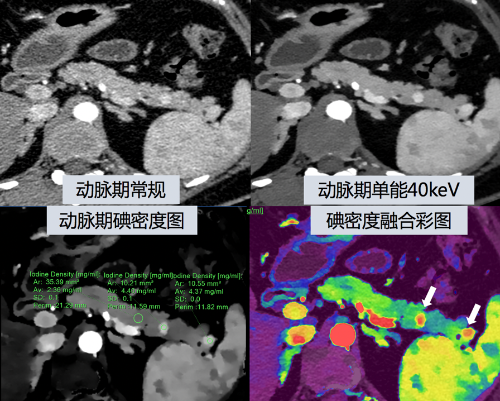

(图2)

光谱CT通过空间上对等的上、下两层探测器,对穿过人体的X射线进行高、低能量分离采集,两套能量信息可以用来进行能量分析、物质识别与定量,可以重建生成虚拟单能量图像、碘密度图及有效原子序数图等多种参数图像。低能量段(<70 keV)的虚拟单能量能够明显提高含碘(增强CT使用的对比剂的主要成分)组织的CT值,可以提高胰岛素瘤病灶与胰腺实质背景的对比度,有利于病灶显示;碘密度图直接量化组织含碘浓度进行成像,可以通过叠加伪彩图像,清晰定位病灶。(图2、图3)